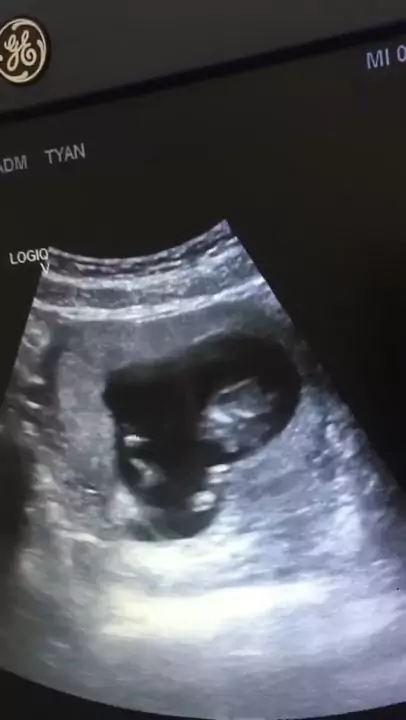

SI JANIN LONCAT-LONCAT DI RAHIM!! USG FULL USIA KEHAMILAN 11 MINGGU / FETAL DEVELOPMENT 11 WEEKS